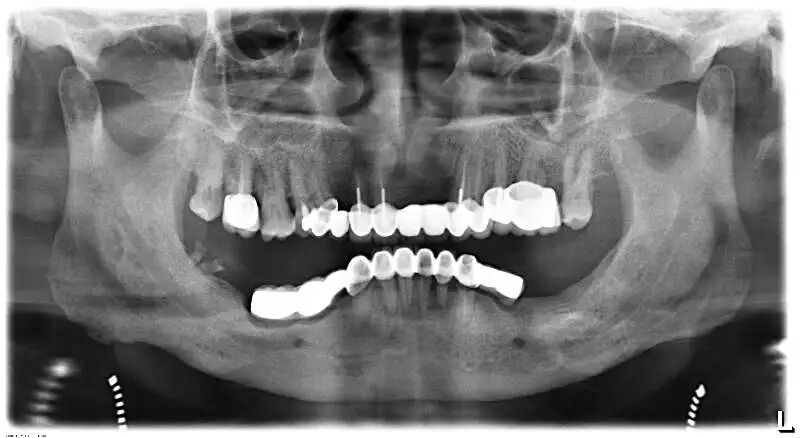

另外,烤瓷桥中的极品——“长江大桥”现象,则是普遍存在于中国各城市各基层牙科的不规范现象,与普通烤瓷桥不同,其本质是一种违反口腔生物力学原理的设计,其最常见的转归是全口牙报废,临床上很多先在基层做,两三年后去医院拆,对口腔健康的影响令人咂舌。

这样的病例实在太多,公立医院和部分高端民营口腔机构每年都要拆除很多例,后续治疗则费时费事费钱费脑筋,而且此类患者来源于社会各阶层,我见过的病例包括一些同事医生(非牙医)的父母,医生的健康意识不代表其家人,而你无法想象其中一例是拥有几百亿资产的企业家,医疗信息不对称应该是主要因素。